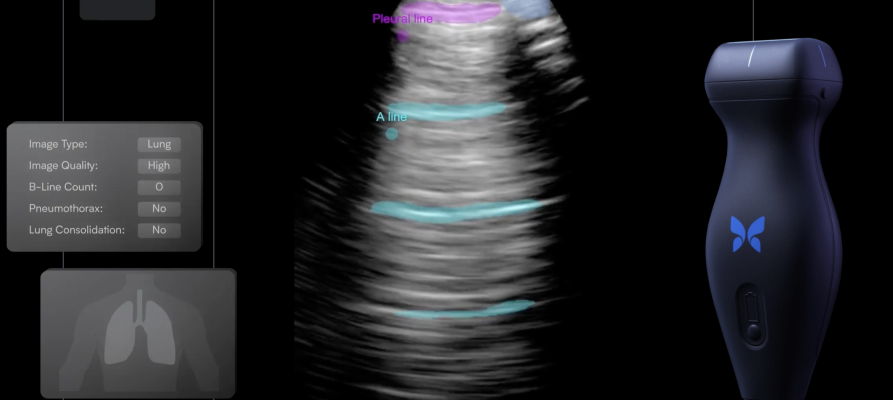

August 3, 2023 — Butterfly Network, Inc. a digital health company transforming care through the power of portable, semiconductor-based ultrasound technology and intuitive software, today announced the release of its software development kit (SDK) for use by third parties. The SDK can be leveraged by artificial intelligence (AI) software developers, medical device companies building ultrasound into their platforms, and telemedicine companies adding ultrasound into their virtual care workflows. The kit will allow developers to utilize Butterfly’s platform to build custom applications that can be commercialized to Butterfly’s customer base – the largest user network in handheld point-of-care ultrasound.1 The Company ultimately plans to open “Butterfly Garden,” an AI Marketplace where new apps will be hosted for Butterfly users to discover and purchase the latest AI capabilities.

- Improve ease of use by augmenting practitioners with image acquisition assistance, automatic clinical measurements, or clinical decision support;